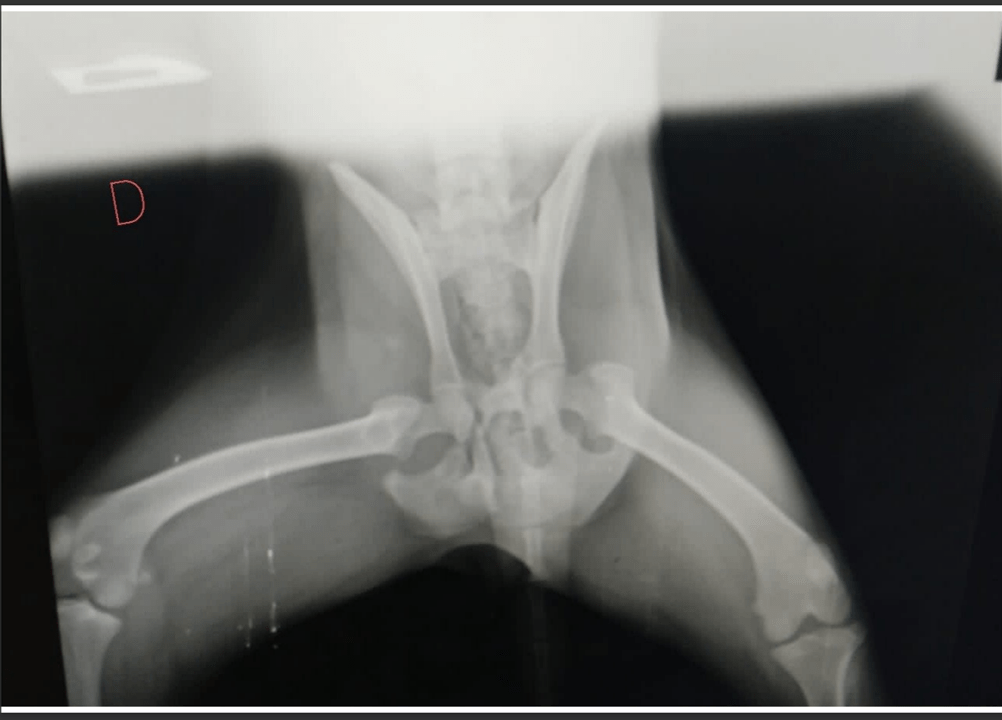

Trixie gets deeply stressed around vets and is always initially nervous of strange men, so it wasn’t a nice experience for her, our stress levels were on par! Then we got the results. Her x-ray images shocked our rescue vet and Dr Pam. Trixie had fractures in her remaining front leg and her left hip that had healed badly. Here are a few of the images:

Thanks for the images; this poor dog! She has a pretty bad pelvic fracture on the right side so her hip joint is not normal. The left hip looks okay and her elbow joint is normal but unfortunately her carpus (wrist) joint is out of place. Most likely the tendon damage pulled the joint apart or she suffered a fracture through the joint plate but either way her joint is not lined up so she is unable to bear weight. Combine that with the fractured pelvis and amputated leg and I am surprised that this girl can even get up.